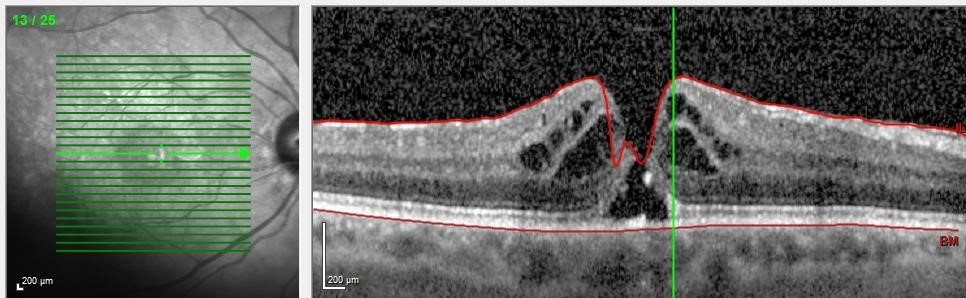

Makula deliği, göz sinir tabakasında en keskin görmenin gerçekleştiği bölgede duysal sinirlerin lokalize defektidir. Başka bir ifade ile tam merkezde sinir katmanında bir boşluk/ delik ortaya çıkar. Delik nedeniyle tam merkezde net görülemeyen bir alan bulunur. Delik bulunan gözle insanların yüzü seçilemeyebilir, yazı okunamayabilir.  Bu boşluk sinirin tüm katlarını etkilemişse cerrahi tedavi gereklidir. Yeni gelişen küçük deliklerin cerrahi ile kapanması ve görmede düzelme oranı yüksektir. Uzun süredir mevcut olan büyük deliklerde ise tedavi ile başarı oranı düşüktür.  Bu nedenle makula deliklerinde görme kaybının engellenmesi açısından erken tanı ve tedavi son derece önemlidir.